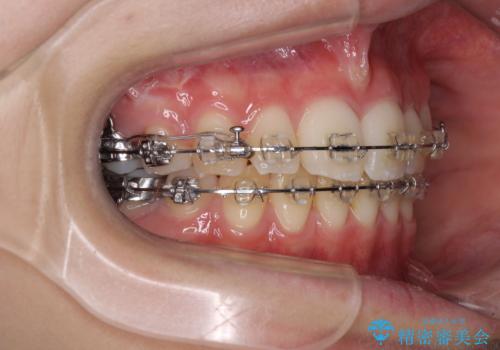

治療途中で転院 抜歯矯正の仕上げ治療

- 地元で抜歯治療を行っている途中、東京へ転職したため治療を継続して欲しいとのことで来院された患者様です。

出っ歯を抜歯矯正にて治療をしていらっしゃいましたが、抜歯スペースが少し残っていたため、閉じて歯列を仕上げていくこととしました。